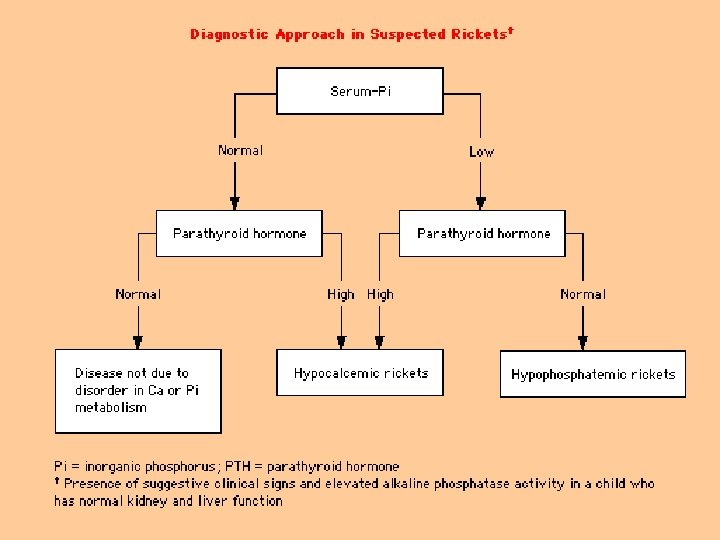

Biochemical findings in rickets n Alkaline phosphatase usually is ↑in all forms of rickets. n Serum phosphorus concentrations usually are↓ in both hypocalcemic and hypophosphatemic rickets. n Serum Ca is ↓only in hypocalcemic rickets. n Serum parathyroid hormone typically is ↑in hypocalcemic rickets, in contrast it is N in hypophosphatemic rickets. n 25 -OH vitamin D reflect the amount of vitamin D stored in the body, and is ↓in vit D deficiency. n 1, 25 -OH 2 vitamin D can be↓, N or ↑in hypocalcemic rickets and usually is N or slightly ↑in hypophosphatemic rickets.

Biochemical findings of rickets n Vitamin D deficiency rickets Low- normal serum calcium level n Increased secretion of PTH (secondary hyperparathyroidism) to compensate for low calcium n Hyperparathyroidism will increase renal excretion of phosphate, leads to low serum phosphate level n Elevated alkaline phosphatase enzyme n Reduced urinary calcium level n Low level of both 25 and 1, 25 - di hydroxy n

Biochemical findings of rickets Hypophosphatemic rickets n Low serum phosphate level n Normal calcium level n Normal parathyroid hormone level n High alkaline phosphatase level n In-appropriate low or normal 1, 25 -di hydroxy vitamin D n phosphate is the major stimulus for 1 hydroxylase